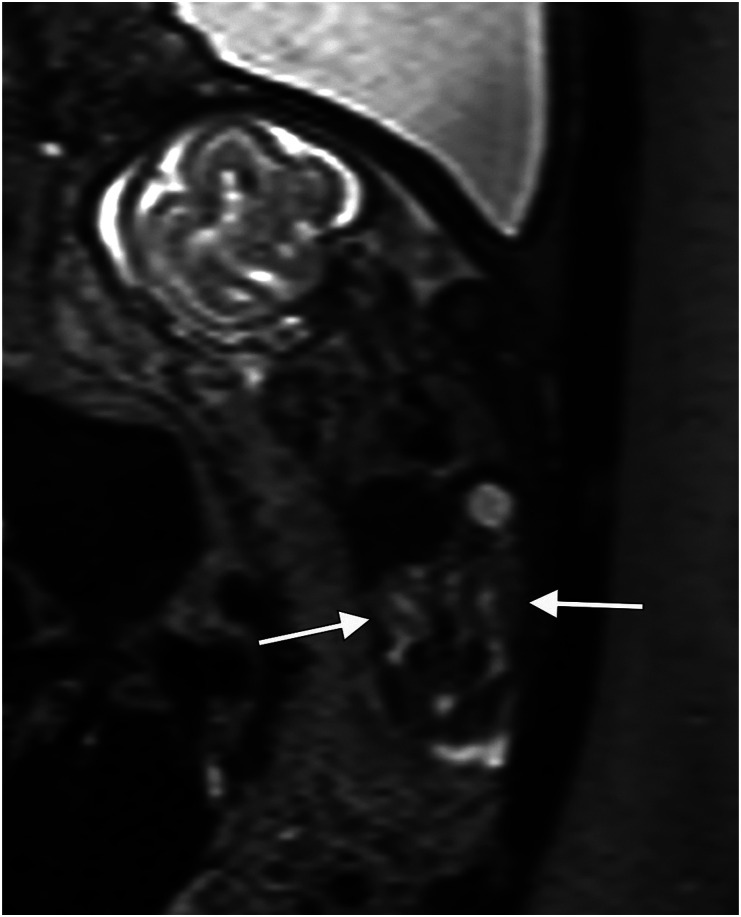

背景:胎儿超声波检查有其局限性,尤其是在患者肥胖或胎粪过少的情况下。核磁共振成像(MRI)可作为补充,但只有少数研究关注妊娠后三个月的检查。目的:验证核磁共振成像作为诊断妊娠后三个月胎儿畸形的补充:这项回顾性研究检索了乌普萨拉大学医院胎儿医学科和放射科 2008 年 1 月至 2012 年 7 月的数据。研究回顾了 121 个胎儿的超声和磁共振成像结果与最终诊断的关系,包括产后随访和尸检结果:结果:在 121 个胎儿中,51 个(42%)确诊或怀疑有中枢神经系统异常,70 个(58%)确诊或怀疑有非中枢神经系统异常。在所有病例中,核磁共振成像为21%的病例提供了额外的信息,但并未改变妊娠管理,而为13%的病例提供的信息改变了妊娠管理。当发现或怀疑中枢神经系统异常时,核磁共振成像为 22% 的病例提供了补充信息,改变了 10% 的病例的治疗方案。非中枢神经系统病例的相应数字分别为 21% 和 16%。在体重指数(BMI)大于 30 kg/m2 的患者(25%)和少腹水患者(38%)中,提供额外信息并改变处理方案的病例比例尤其高。在 5 例 III 类病例中,发现了假阳性超声检查结果:结论:妊娠后三个月的核磁共振成像是超声检查的补充,可提高对胎儿中枢神经系统和非中枢神经系统畸形的诊断率,尤其是在少子水肿或孕妇肥胖的情况下。

Conclusions: MRI in the second trimester complements ultrasound and improves diagnosis of fetal CNS- and non-CNS anomalies especially when oligohydramnios or maternal obesity is present.